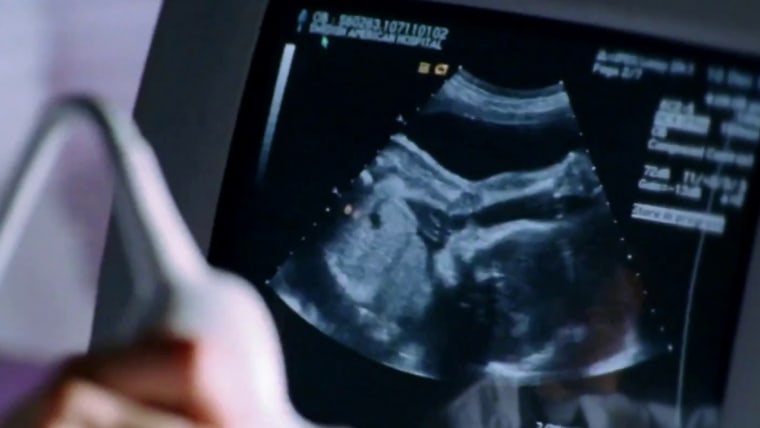

Concerns for pregnant women as CDC warns of rise in parvovirus

In recent years, parvovirus infected about 3% of Americans. Now the number has tripled. NBC News' Anne Thompson speaks to a patient who contracted the virus this spring. Thirty weeks pregnant and in the hospital, she’s dealing with serious complications including her placenta not pushing enough blood to bring her son critical oxygen and nutrients.